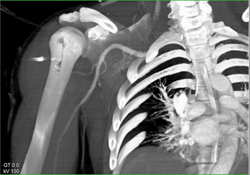

Melanoma